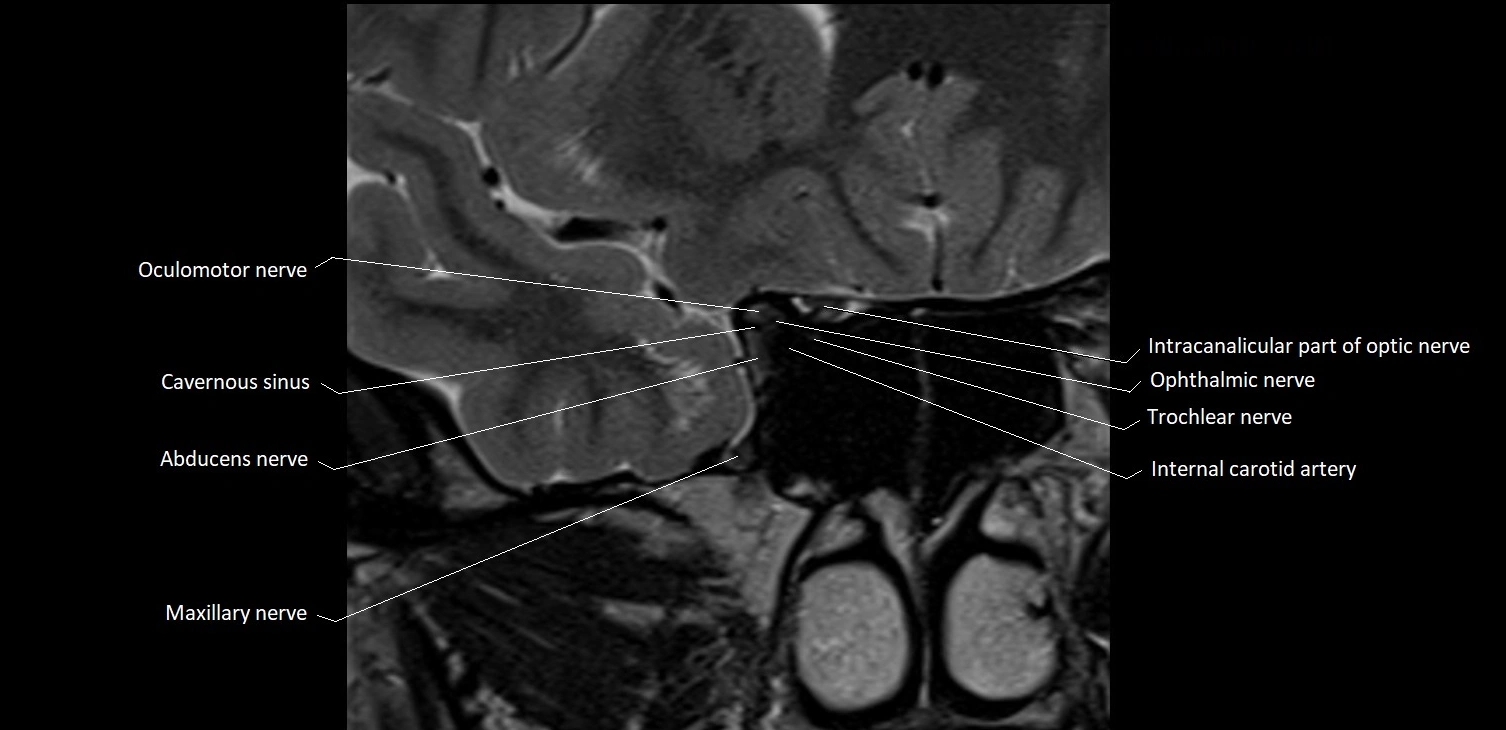

Seen as a hypointense (dark) line running from the brainstem at the pontomedullary junction, traversing the prepontine cistern, and entering Dorello’s canal under the petrosphenoidal ligament, then into the cavernous sinus, and finally the orbit

MRI images